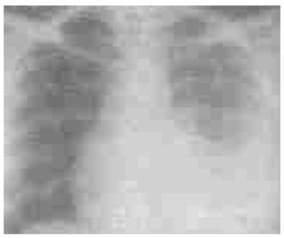

A number of potential problems can be encountered if antiretroviral therapy (ART) and anti-TB therapy (AKT) are

prescribed concurrently. These include overlapping toxicities, increased pill burden and risk of sub-optimal

adherence, drug-drug interactions and inflammatory reactions.

For patients with active TB in whom HIV infection is diagnosed and ART is required, the first priority is to

initiate standard anti-TB treatment. The optimal time to initiate ART is not known. Case-fatality rates in

patients with TB during the first two months of TB treatment are high, particularly in settings with a high

prevalence of HIV, suggesting that ART should begin early. On the other hand, considerations of pill burden,

drug-drug interactions, toxicity, and immune reconstitution inflammatory syndrome (IRIS) support the later

initiation of ART

Thus, a balance needs to be established between the risk of disease progession and death it ART is deferred,

against an increased risk of inflammatory reactions and other adverse events if ART is started rapidly after TB

diagnosis.

The WHO (2006) recommendations are as follows:

In patients with CD4 counts <200 cells/mm3: ART should be started as soon as the patient

has tolerated and stabilized on TB treatment. It usually takes between 2 and 8 weeks after the start of TB

treatment.

In patients with CD4 counts >200 ceils/mm3: Initiation of ART may be delayed until after

the initial intensive phase of TB treatment has been completed.

In patients with CD4 counts >350 cells/mm3: ART can be delayed until after the

completion of short-course TB therapy, following a reassessment of the patient's eligibility for ART and

evaluation of the response to TB therapy and of CD4 counts, if available.